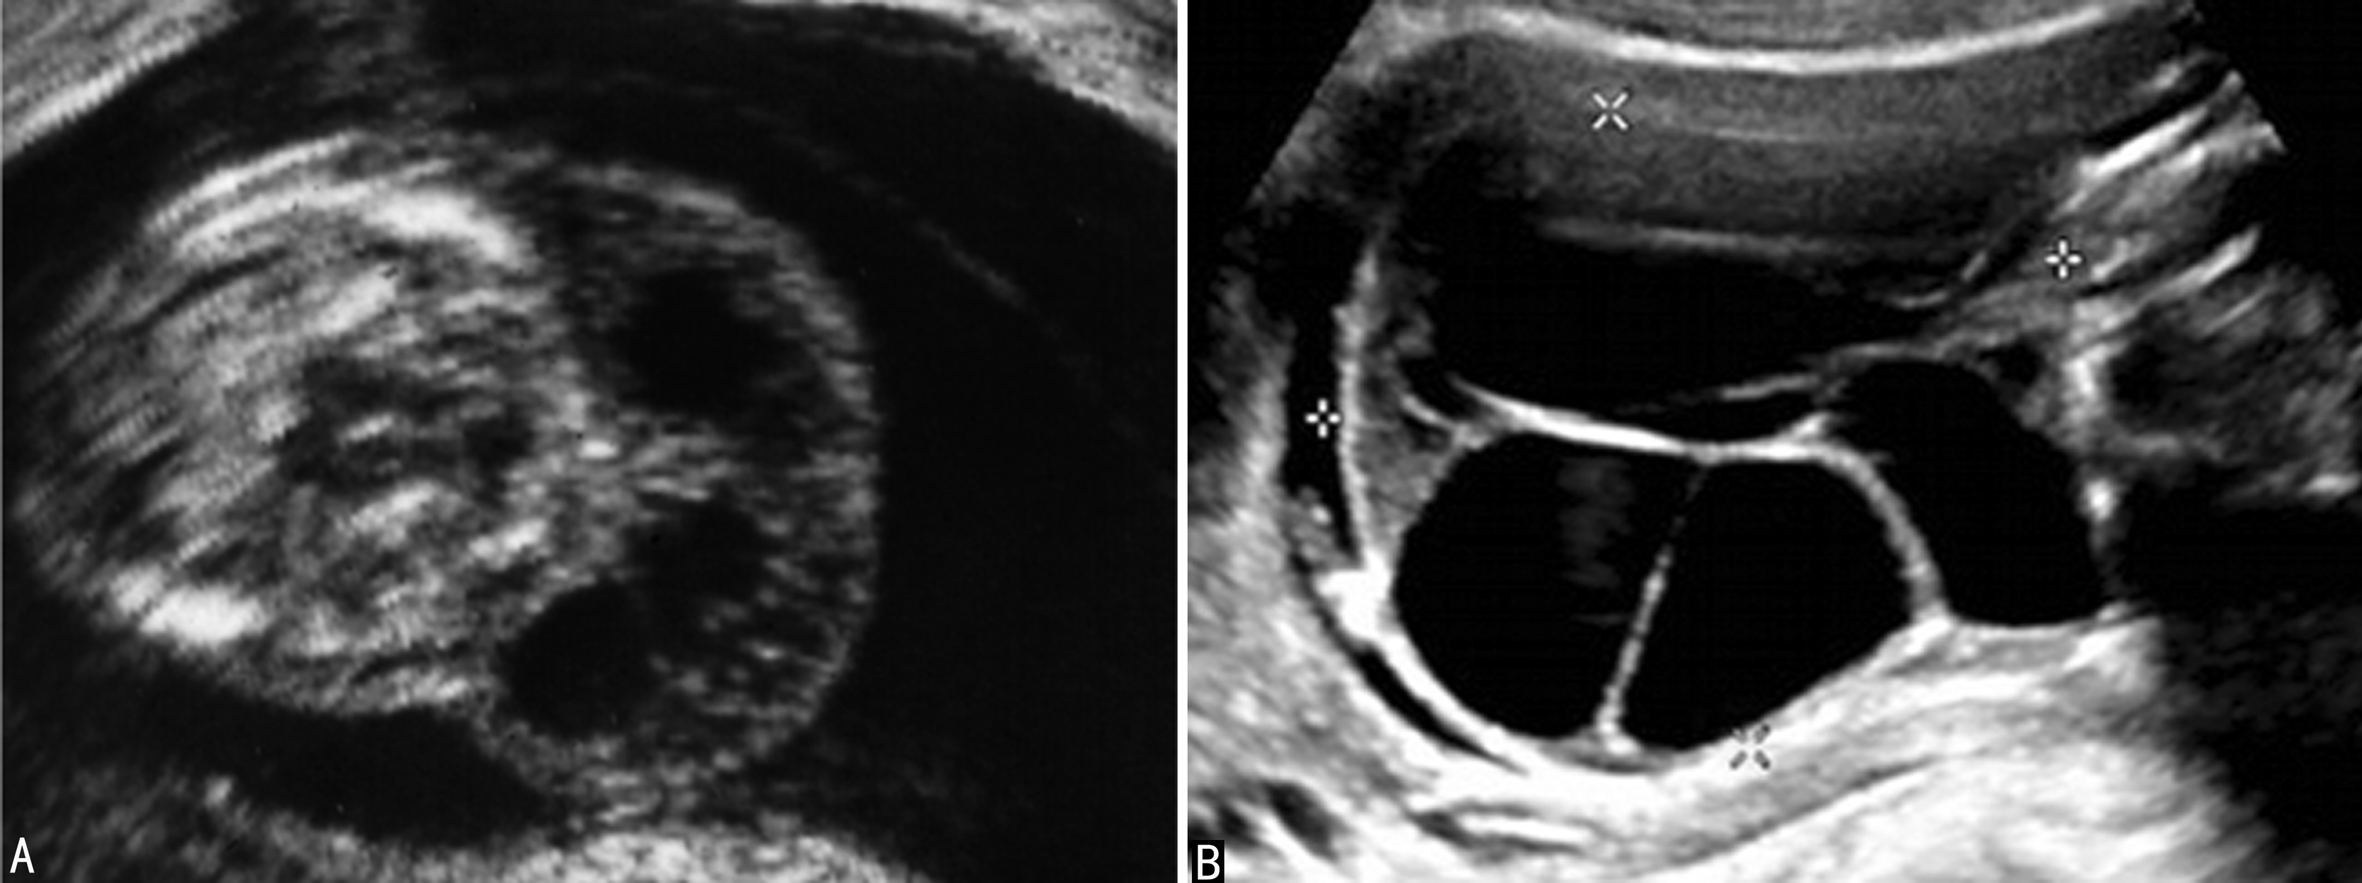

(一)水囊状淋巴管瘤

水囊状淋巴管瘤系来自淋巴系统的囊性包块,以颈部两侧及后外侧多见,显示为多房分隔状无回声区或无分隔的无回声区(图1)。产前超声显像检查比较容易显示颈部水囊状淋巴管瘤,其出现与染色体异常有明显的关系。有报道认为60%~70%的水囊状淋巴管瘤存在非整倍体,并且以Turner综合征 (45, X)常见,其他还见于18-三体综合征、13-三体综合征和 21-三体综合征。为观察水囊状淋巴管瘤分隔与不分隔的意义,Bronshtein等用了5年的时间观察了125例无分隔水囊状淋巴管瘤和25例多房性水囊状淋巴管瘤的胎儿,并与其染色体核型分析、形态学和组织学外观以及妊娠结局进行比较,发现早期妊娠中有98%的无分隔水囊状淋巴管瘤仅短暂显示,而多房的水囊状淋巴管瘤中仅有44%;更重要的是前者仅有5.7%的异常核型发生,后者高达72%;胎儿水肿的发生率在前者仅为1.7%,后者为40%;活产率在前者是94%,后者是12%。与颈部比较,在非典型部位发生的水囊状淋巴管瘤其患非整倍染色体的危险性较低。类似的结论也被以后的研究证实。

图1 胎儿颈部水囊状淋巴管瘤